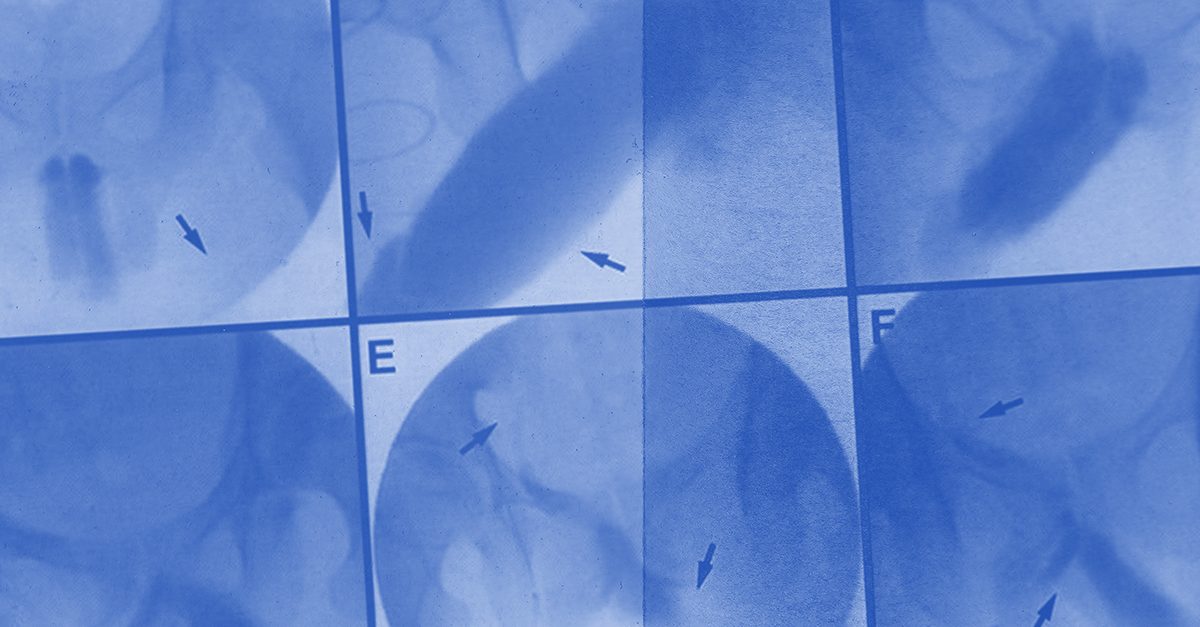

Diagnosing venous leak

A commonly used diagnostic tool for a venous leak is the penile duplex Doppler ultrasound (PDDU), which measures blood flow in the penis in centimeters per second. For peak systolic velocity (PSV), 30 centimeters per second or greater of arterial blood flow is considered normal. The end-diastolic velocity (EDV), which measures blood flow leaving the penis through the veins, should be less than 3 centimeters per second.

Hsieh performs the PDDU in two phases, once when the patient has a flaccid penis and again when they have an erection.

"If I see abnormal blood flow in the arteries or the veins with an erection when compared to the flaccid state, that's how we make these diagnoses," he said.

For example, if a patient has a normal PSV reading but an elevated EDV of, let's say 6, that would be considered venous leak, said Seth Cohen, M.D., an assistant professor of urology and director of sexual medicine at NYU Langone Health. The arteries are delivering plenty of blood flow to the penis, but the blood is just leaking right back out.